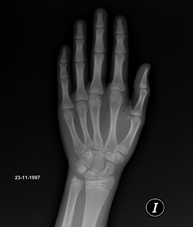

- RX Edad ósea

Estudio que mediante una radiografía de la mano permite valorar, en función del desarrollo de los huesos, la edad del paciente y determinar si existe un retraso o un crecimiento superior a lo que corresponde para su edad.